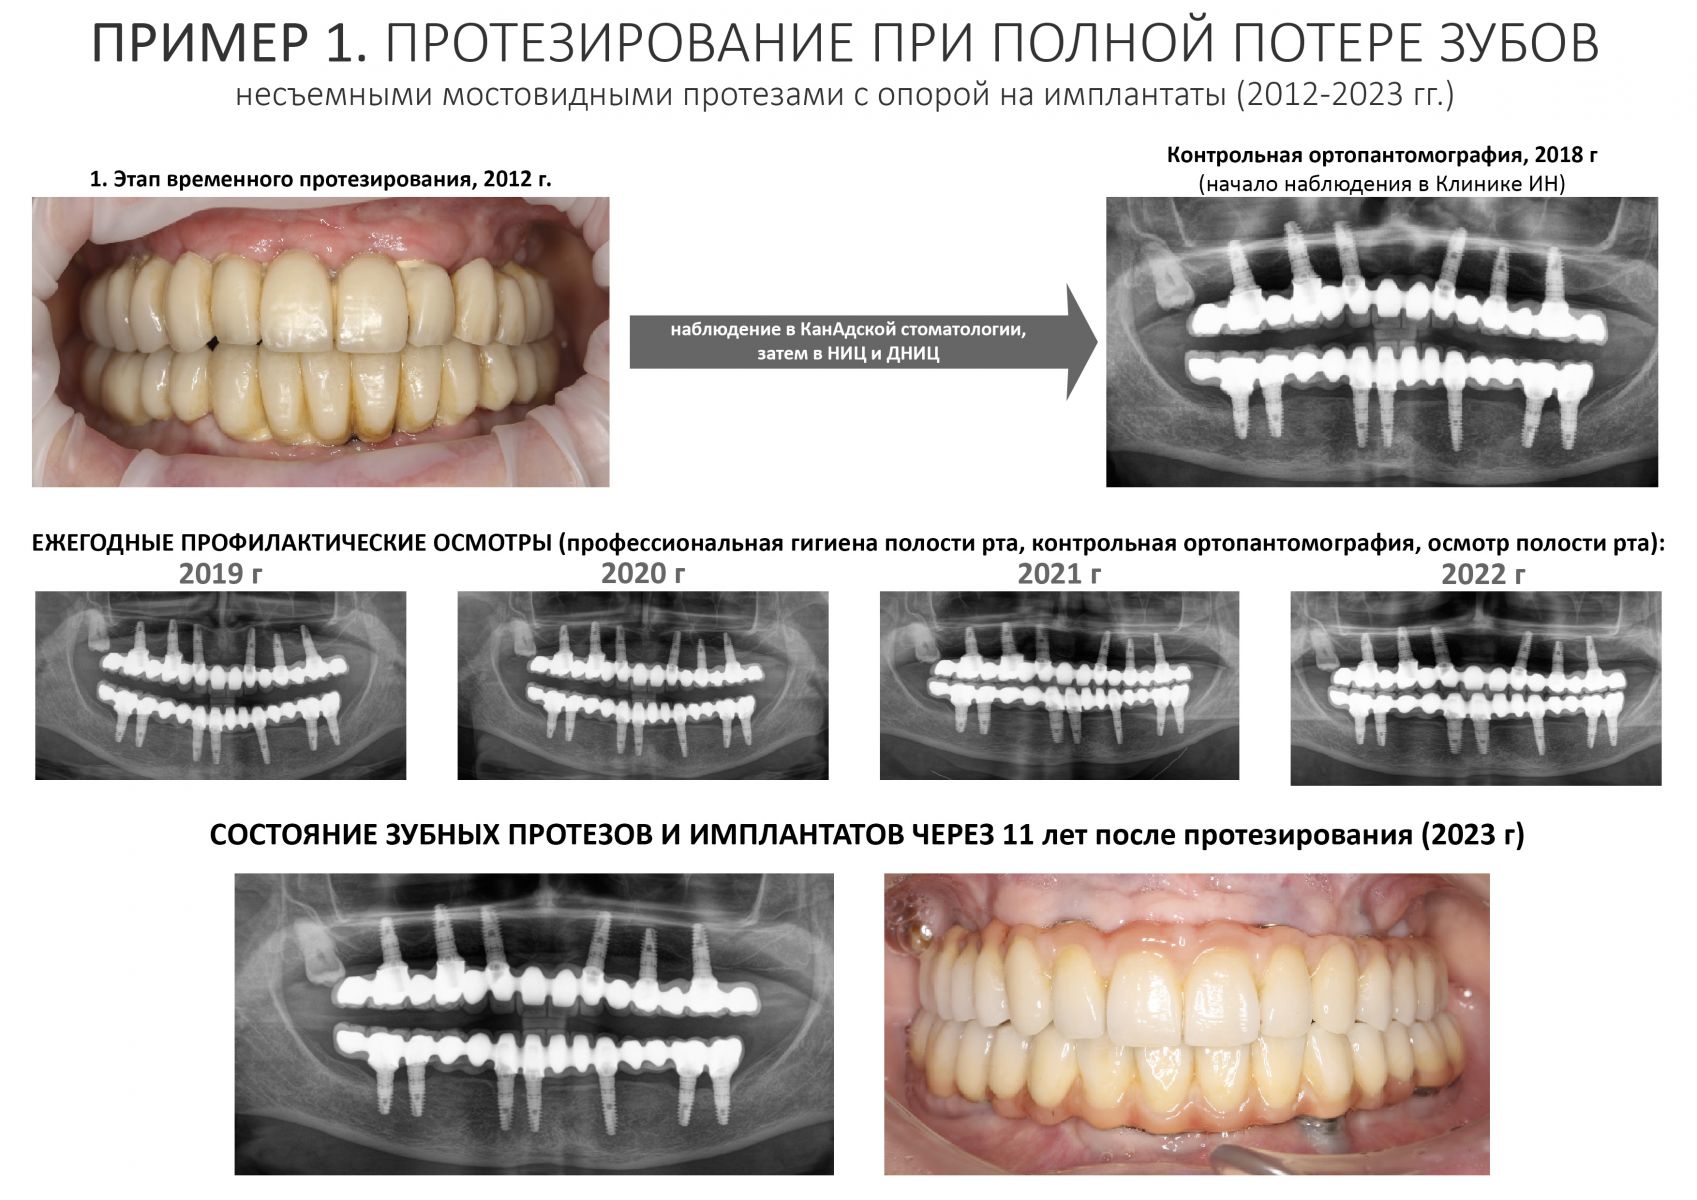

Это пациентка уютной Клиники ИН. Я установил имплантаты Xive одиннадцать лет назад, когда работал в «канАдской стоматологии». Там же её протезировали. По неизвестной науке причине, врач-ортопед выбрал, мягко говоря, неоднозначное протетическое решение — на каждый из тринадцати имплантатов был изготовлен индивидуальный абатмент, а сами зубные протезы были приклеены к ним специальным цементом. Так делать нельзя (объяснение здесь>>). Если бы сейчас кто-то из моих докторов сделал что-то подобное — вмиг погнали бы из клиники ссаными тряпками. С другой стороны, врач-ортопед (он же главный врач «канАдской» на тот момент) в миру известен как жадина и барыга — это вполне может быть причиной выбора цементной фиксации и индивидуальных абатментов там, где этого делать нельзя. К сожалению, иногда бабло побеждает добро.

Но главной проблемой подобного протетического решения является отнюдь не цена. Цементная фиксация не позволяет добраться до имплантатов в случае необходимости, поэтому любая проблема, будь то периимплантит или просто скопившийся зубной камень — это уничтожение существующего протеза и повторное протезирование со всеми вытекающими. Поэтому каждый раз, когда пациентка приходила на профилактический осмотр, я ждал контрольный снимок с замиранием сердца — очень уж переживал, что придется всё переделывать.

К счастью Елена (так зовут пациентку) оказалась очень ответственной: каждый год она приходит в нашу уютную Клинику ИН, мы делаем контрольные снимки, проводим профессиональную гигиену полости рта, которую она в течение года поддерживает гигиеной индивидуальной. Она помнит, чего стоило проведенное лечение как по финансам, так и с точки зрения нагрузки на её хрупкий женский организм, потому никогда не пропускает профилактические осмотры.

Собственно, я не зря выбрал в качестве примера столь нетривиальный и даже спорный клинический случай. Он наглядно демонстрирует, что выполнение пациентом рекомендаций по уходу и профилактическим осмотрам обеспечивают длительный срок службы имплантатов даже тогда, когда протетическая конструкция этого, вроде как, не предполагает. Иными словами, «несмотря на все усилия врачей, пациент остался жив» — и продолжает жить полной жизнью, посещая уютную Клинику ИН раз всего раз в год.